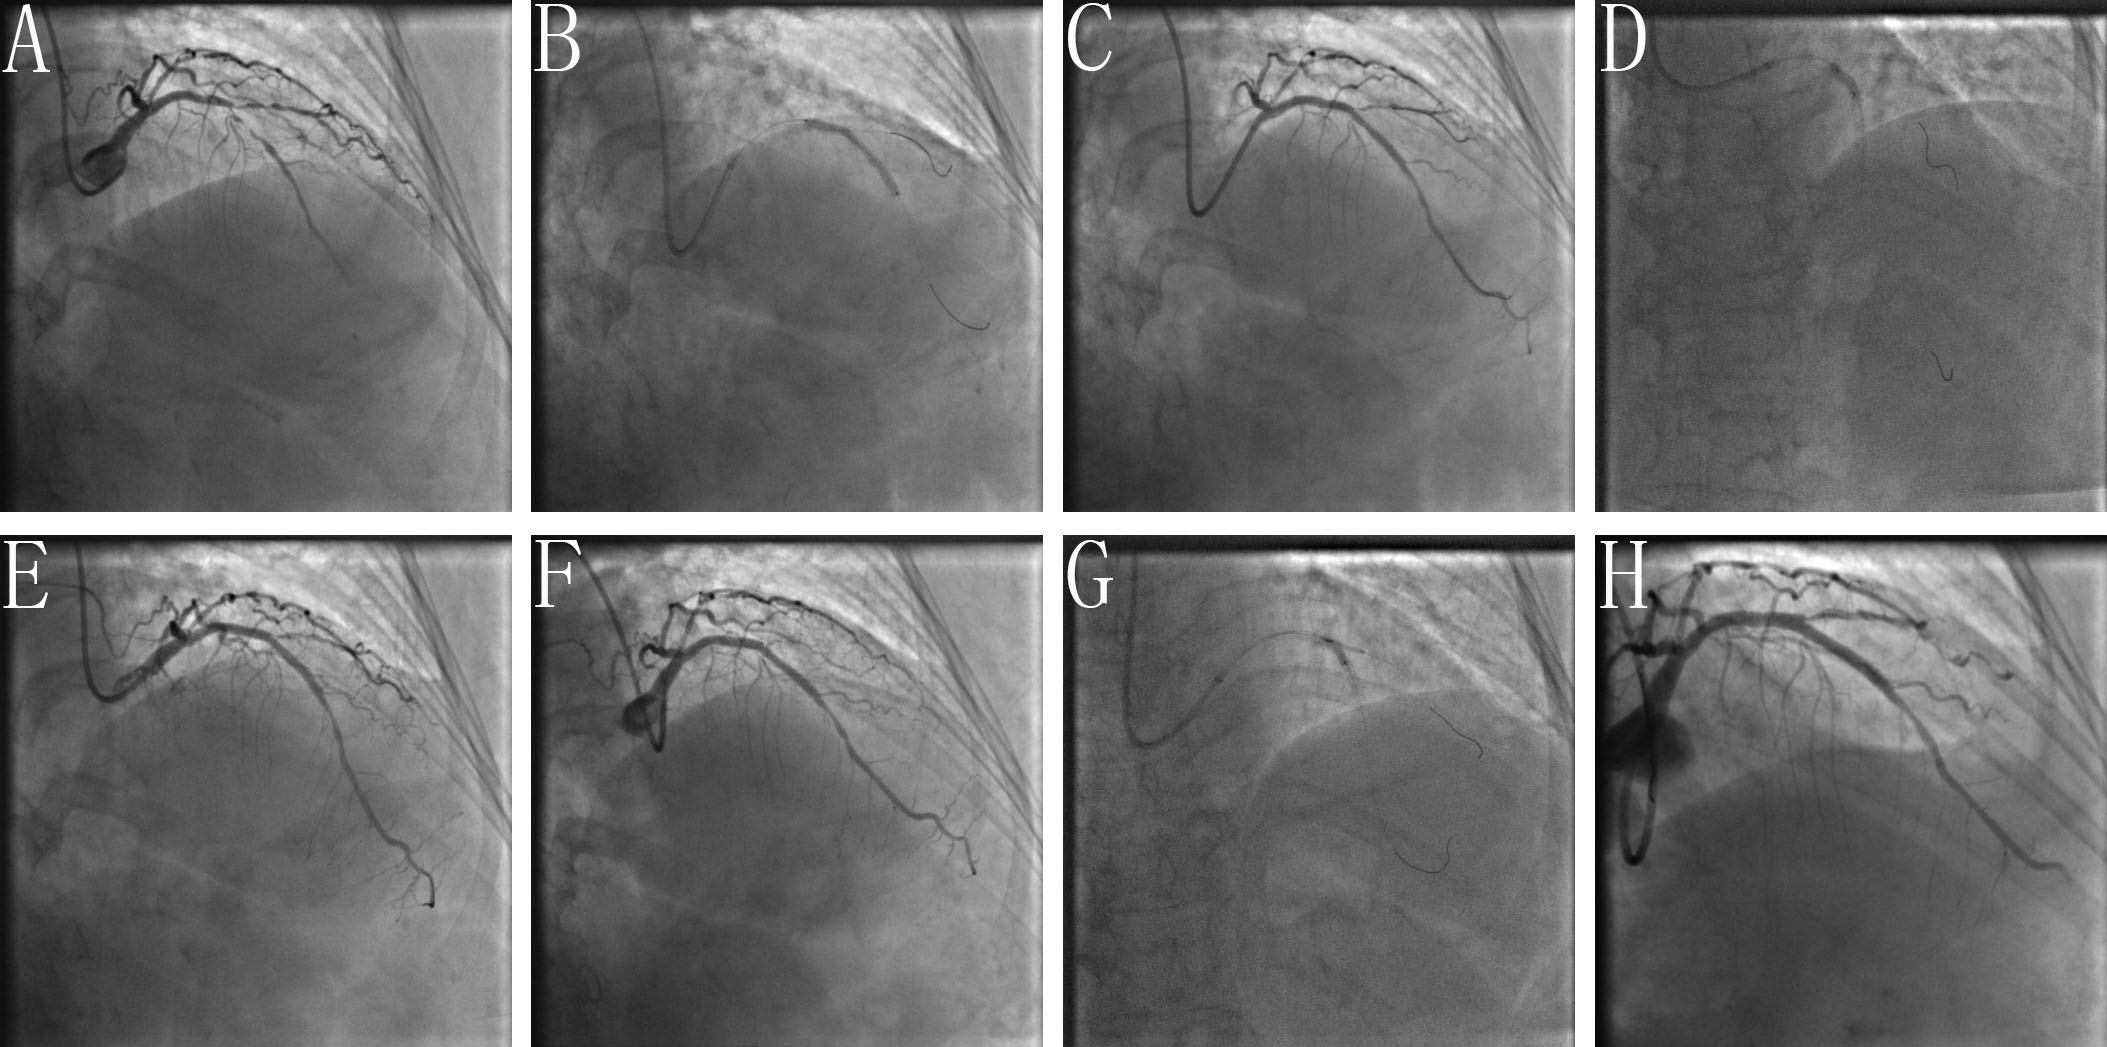

POTA: Briefly, after MV stenting, at least one of the POTAs (e.g., POT-alone, POT-S-POT, POT-K-POT) were used at the discretion of the operators. A clinical example and final results using the BOOT and POTA for treating an unstable angina patient with a severe LAD-D1 TCBL are shown by coronary angiography in Figs. 2,3, respectively.

Fig. 3.Clinical practice of the POTA technique. (A) Baseline angiogram with significant stenosis of the left anterior descending (LAD)/second diagonal bifurcation (D1) (medina classification: 1, 1, 1). (B) After pre-dilation of LAD and D1, the stent is positioned covering the lesion of proximal-mid LAD with pre-imbedding a guidewire to avoid the D1 acute occlusion. (C) Rewiring the D1 through the most distal cell of the LAD stent facing the SB. (D) Performing POT with NC balloon after rewiring. (E) Angiogram shown TIMI 3 blood flow of D1 with non-dissection. (F) Acute occlusion of D1 after guide wire withdrawal. (G) Performing FKBD after rewiring LAD and D1. (H) Final angiogram shown TIMI 3 blood flow of LAD with non-residual in-stent stenosis, but type B dissection of proximal D1 with TIMI 3 blood flow.